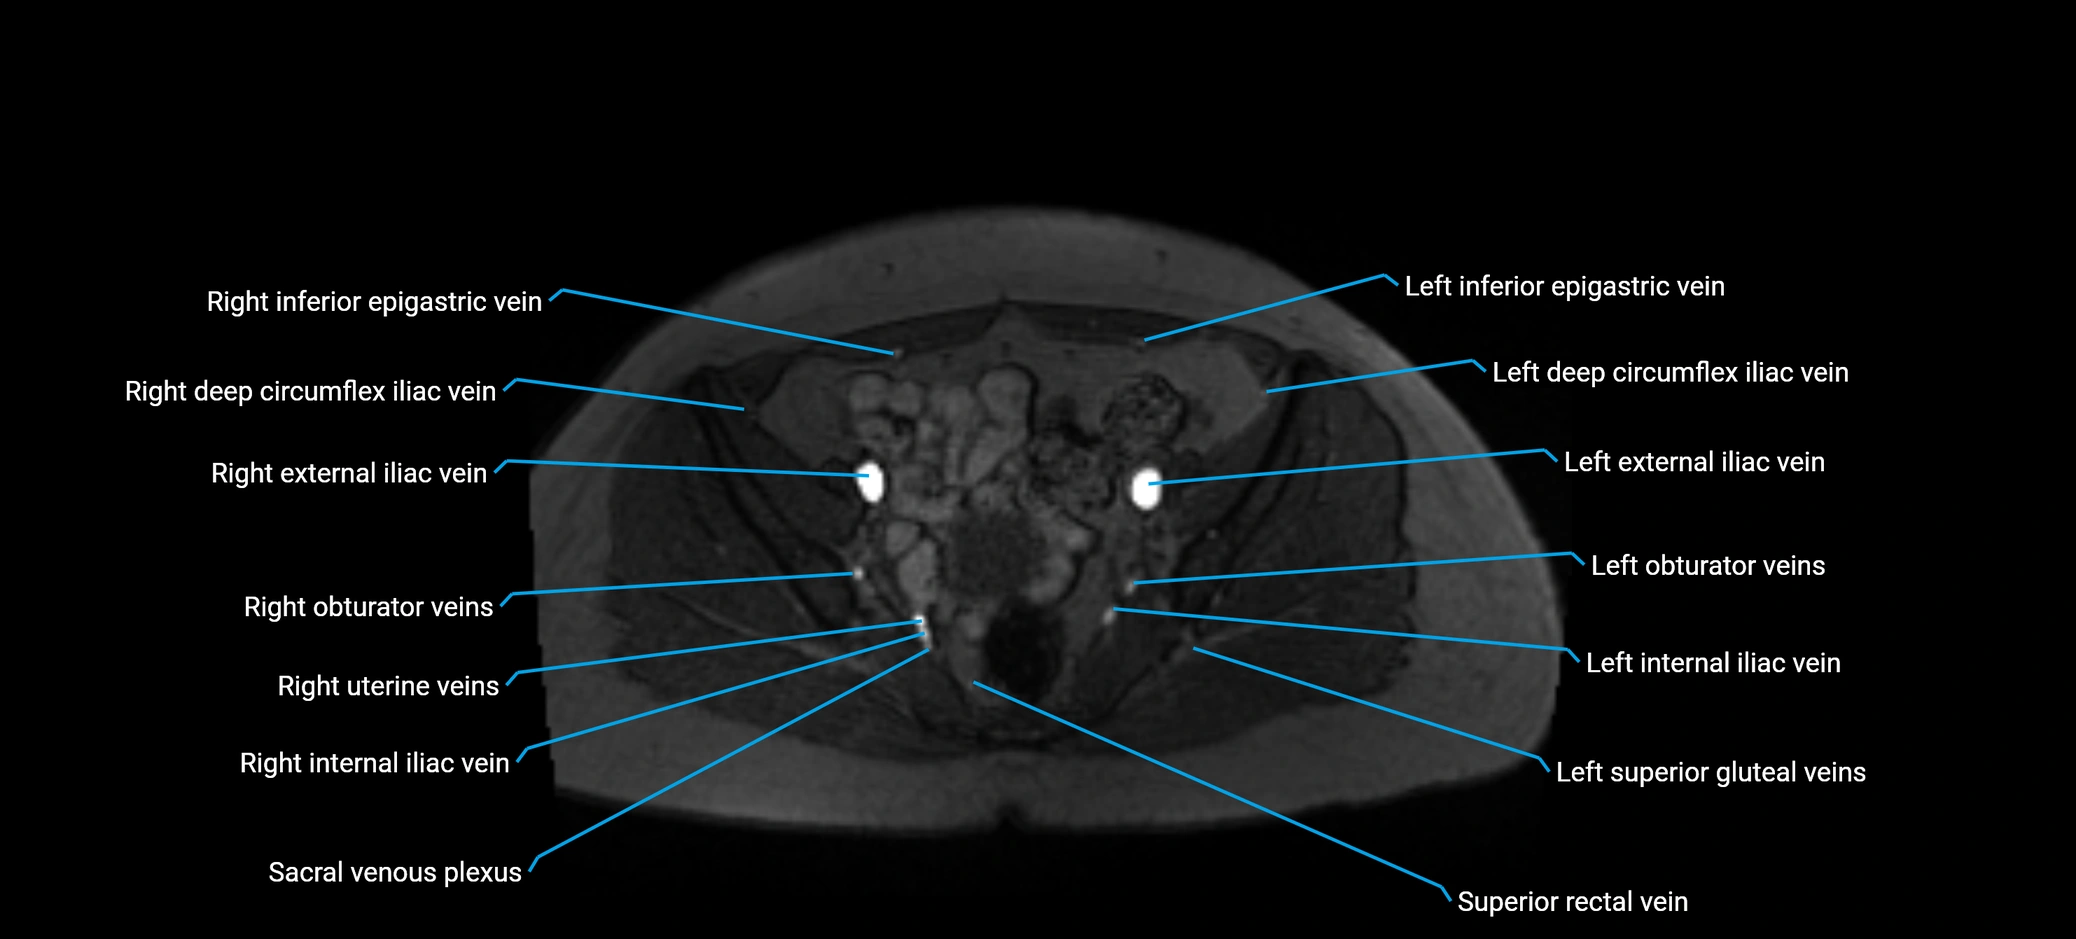

MRI image

image